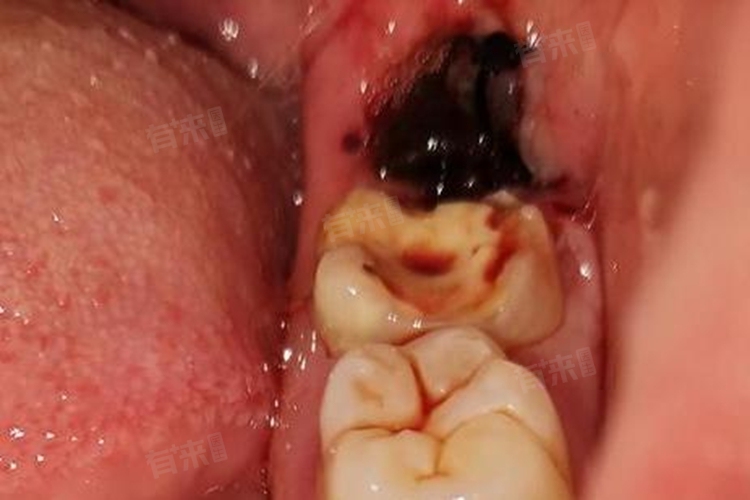

- 从创口愈合的过程来看,拔牙后的头几个小时是关键时期,血凝块的形成对于止血至关重要。如果血凝块过早脱落,可能会导致再次出血。在这段时间里患者应尽量避免漱口、吸吮创口、剧烈运动等行为,以免破坏血凝块。

- 一般24小时后创口处的血凝块会逐渐稳定,出血的风险大大降低。但在接下来的几天里患者仍需注意口腔卫生,避免食用辛辣、刺激性食物,以免刺激创口引起出血。